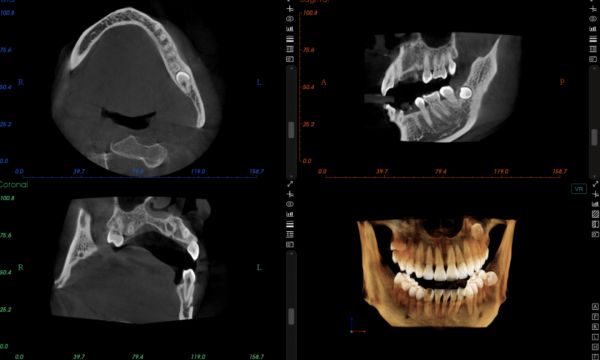

△口腔CT影像

丁鹏认为,智能化的产品将连接、整合、推动整个行业,催生出新的模式甚至新的业态,必将是口腔产业下一个黄金十年发展的根本驱动力。2020年,DeepCare完成了基于口腔曲面体层放射影像的AI分析功能,并且将会长期扎根口腔领域,并计划2025年之前,完成由AI驱动的口腔分析平台建设。

牙片在医疗当中有需求吗?答案毫无质疑的。直接扫描患者口腔内获取三维信息的牙片,可以直观的分析患者的口腔详情,从而帮助医生更好的判断疾病,大大节约了患者的看病时间和看病体验。尽管口扫设备昂贵,但依然被众多口腔医院所采用。据《世界牙科技术》杂志估计,2016年,已经约5%-10%的牙科医生使用口内扫描仪获取数字印模,并且这一数字在快速提升。

从临床上看,相比较大影像和视网膜病种的复杂性和多样性,牙片的标准化程度更高,目前大概有四种:阻生智齿牙片、牙周病牙片、根尖周病牙片、正常牙片,牙片诊断更加容易。当然,疑难杂症除外。